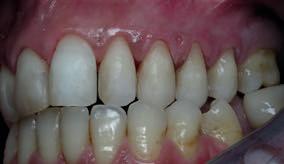

Embora a proposta inicial ortodôntico-cirúrgica fosse, no nosso entender, a mais indicada para tratar o caso, a realidade é que a opção escolhida preencheu satisfatoriamente os objetivos iniciais da paciente, fazendo-o de forma mais rápida, menos invasiva e mais confortável. No entanto, condicionou a estética final, no sentido em que os dentes 11, 21, 22 e 23 ficaram com uma proporção altura/largura maior que a ideal, devido à posição inicial da gengiva, que se manteve. Só com ortodontia é que se poderia extruir esses dentes para melhorar a posição da gengiva. Ora, para corrigir a inversão da curvatura da linha incisal dos dentes anteriores e descruzar a mordida anterior era necessário baixar a posição do bordo incisal. Só que, com isso, infelizmente, passou a existir a referida discrepância na proporção altura/largura dos dentes anteriores.

O dente 21 apresentava uma grande perda estrutural: tinha uma lesão CL III mesial e outra distal para além da cavidade de acesso endodôntico. Estava por isso em alto risco de fratura11. Para diminuir esse risco, foi decidido recobrir toda a face palatina com compósito direto, como se de uma faceta palatina se tratasse (Fig. 2- outubro 2010).

Para além disso sabíamos que, segundo Pascal Magne, a colocação de uma faceta vestibular feldspática iria recuperar quase totalmente a resistência perdida11. Não se colocou nenhum espigão. Pode-se notar nas fotos uma deterioração da interface cerâmica-compósito que poderá ser facilmente reparada com aplicação de ácido fluorídrico na cerâmica da interface e jateamento do compósito, seguido de adesivo e compósito fotopolimerizável. No final do branqueamento interno deste mesmo dente, constatou-se que ele se encontrava demasiado claro, porque a paciente ficou 3 meses com o perborato de sódio presente na cavidade de acesso, devido a ter sido submetida a cirurgia abdominal e ter ficado por isso impedida de vir à consulta retirá-lo no devido tempo. No entanto, a faceta colocada mascarou esse indesejado “hiperbranqueamento”.

De assinalar que o desgaste do esmalte vestibular, proximal e incisal dos dentes preparados foi quase nulo e a preservação da vitalidade pulpar foi conseguida em todos os dentes (Fig. 3).